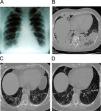

Presentamos el caso de una mujer de 51 años con antecedente de psoriasis diagnosticada 20 años antes con confirmación histopatológica y sin tratamiento. Comenzó un mes antes con un cuadro de tos seca y disnea progresiva, con exacerbación de sus lesiones de psoriasis, por lo que consultó en otro centro donde le realizaron radiografías de tórax. Ante la presencia de opacidades bilaterales, sumado al cuadro clínico presente, se le indicaron antibióticos. Continuó con los mismos síntomas, a lo que se le agregó febrícula. Se la medicó con 2 esquemas más de antibióticos sin obtener respuesta, por lo que decidió consultar en nuestro centro. Al momento de la consulta se encontraba con fiebre (38,3°C), taquipneica (36x′) y con rales crepitantes secos en ambos campos inferiores pulmonares. La saturación de oxígeno era del 82%. Ante este cuadro se decidió la internación, se comenzó con oxígeno, ventilación no invasiva (VNI) y demás soportes de la UCI. Se le efectuó una radiografía de tórax (fig. 1A), que mostró opacidades en ambas bases, análisis de laboratorio con leucocitos 9.300 μl, VSG de 83mm, gases arteriales con Ph de 7,43, presión de oxígeno de 53mmHg, presión de anhídrido carbónico de 32mmHg y saturación de oxígeno del 83%; el resto de la analítica fue normal e incluyó hemograma, hepatograma completo, creatininemia, uremia, calcio, sodio, potasio, proteínas totales, albúmina, tirotrofina y colesterol. Se realizó una tomografía de tórax de alta resolución, donde se hallaron extensas áreas parcheadas con ocupación del espacio aéreo y otras de vidrio esmerilado en ambos lóbulos inferiores con zonas con broncograma aéreo (fig. 1B). Ante este hallazgo se le realizó una broncoscopia con lavado broncoalveolar (BAL y biopsia transbroquial en los segmentos más comprometidos de la tomografía. Inmediatamente se le inició tratamiento con esteroides (meprednisona) en dosis de 1,5mg/kg. El resultado del BAL) fue negativo para tuberculosis, hongos y gérmenes comunes, y se halló predominio de linfocitos. Se realizó un análisis de colagenograma, que fue normal como así también serología para VIH y micoplasma, Chlamydia y citomegalovirus: todos fueron negativos. El resultado de las biopsias arrojó el diagnóstico de neumonía organizada. La paciente evolucionó positivamente en los días posteriores y al cuarto día pasó a sala general, donde se le realizó una radiografía que mostró una evidente mejoría. La saturación de oxígeno fue del 94% y una espirometría arrojó un volumen espirado forzado (VEF1) del 67% y una capacidad vital forzada (CVF) del 58%. En el test de 6min caminó 374 m y llegó a una saturación mínima del 88%. Se le dio el alta con meprednisona en dosis de 60mg/día. Se la controló en consultorio externo y evidenció una clara mejoría del cuadro clínico y de la saturación de oxígeno. Al mes, la espirometría arrojó un VEF1 del 79% y una CVF del 71%. En el test de 6min caminó 453 m con saturación mínima del 93%. Se le realizó una tomografía que evidenció la persistencia de un mínimo infiltrado en los lóbulos inferiores (fig. 1C). Después de 3 meses de tratamiento con esteroides en descenso, la paciente se hallaba asintomática con una tomografía (fig. 1D) que mostraba una desaparición prácticamente completa de las opacidades, con VEF1 del 83% y CVF del 84%, y en el test de 6min caminó 519 m sin desaturación.

La neumonía organizada es una enfermedad pulmonar intersticial caracterizada por presentar un cuadro clínico subagudo consistente en tos, disnea y fiebre, con manifestaciones radiológicas caracterizadas por infiltrados alveolares o intersticiales, en ocasiones migratrices2. La tomografía computarizada demuestra como hallazgos más frecuentes consolidaciones parenquimatosas, vidrio deslustrado, dilataciones bronquiales y nódulos centrolobulillares3. El cuadro histopatológico es el de una reparación tisular inespecífica con ocupación de espacios aéreos distales por yemas de tejido fibroinflamatorio laxo que se extienden de un alvéolo a otro a través de los poros de Kohn y ocasiona una distribución de la afectación parcheada en torno a pequeñas vías aéreas. Puede ser secundaria a diversas etiologías, entre las que se encuentran drogas, tóxicos, infecciones, enfermedades autoinmumnitarias y radioterapia, o lo que se denomina neumonía organizada criptogenética cuando no se reconoce la causa2. En el diagnóstico es fundamental la confirmación histopatológica por biopsia transbronquial o quirúrgica y el tratamiento de elección son los esteroides orales, cuyo uso se asocia a una respuesta positiva en la mayoría de los casos4. El término neumonía organizada reemplaza, por consenso, al anterior de bronquiolitis obliterante con neumonía organizada para definir mejor la localización del proceso inflamatorio.